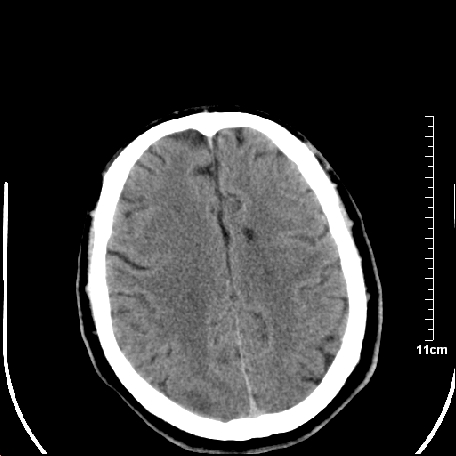

外伤患者,什么病,

外伤患者,没什么症状,

双侧外侧裂,左侧脑沟见高密度结节影,边清,还有鞍上池层面密度也高

1.左额叶脑软化灶。

2.老年脑,基底动脉硬化迂曲。